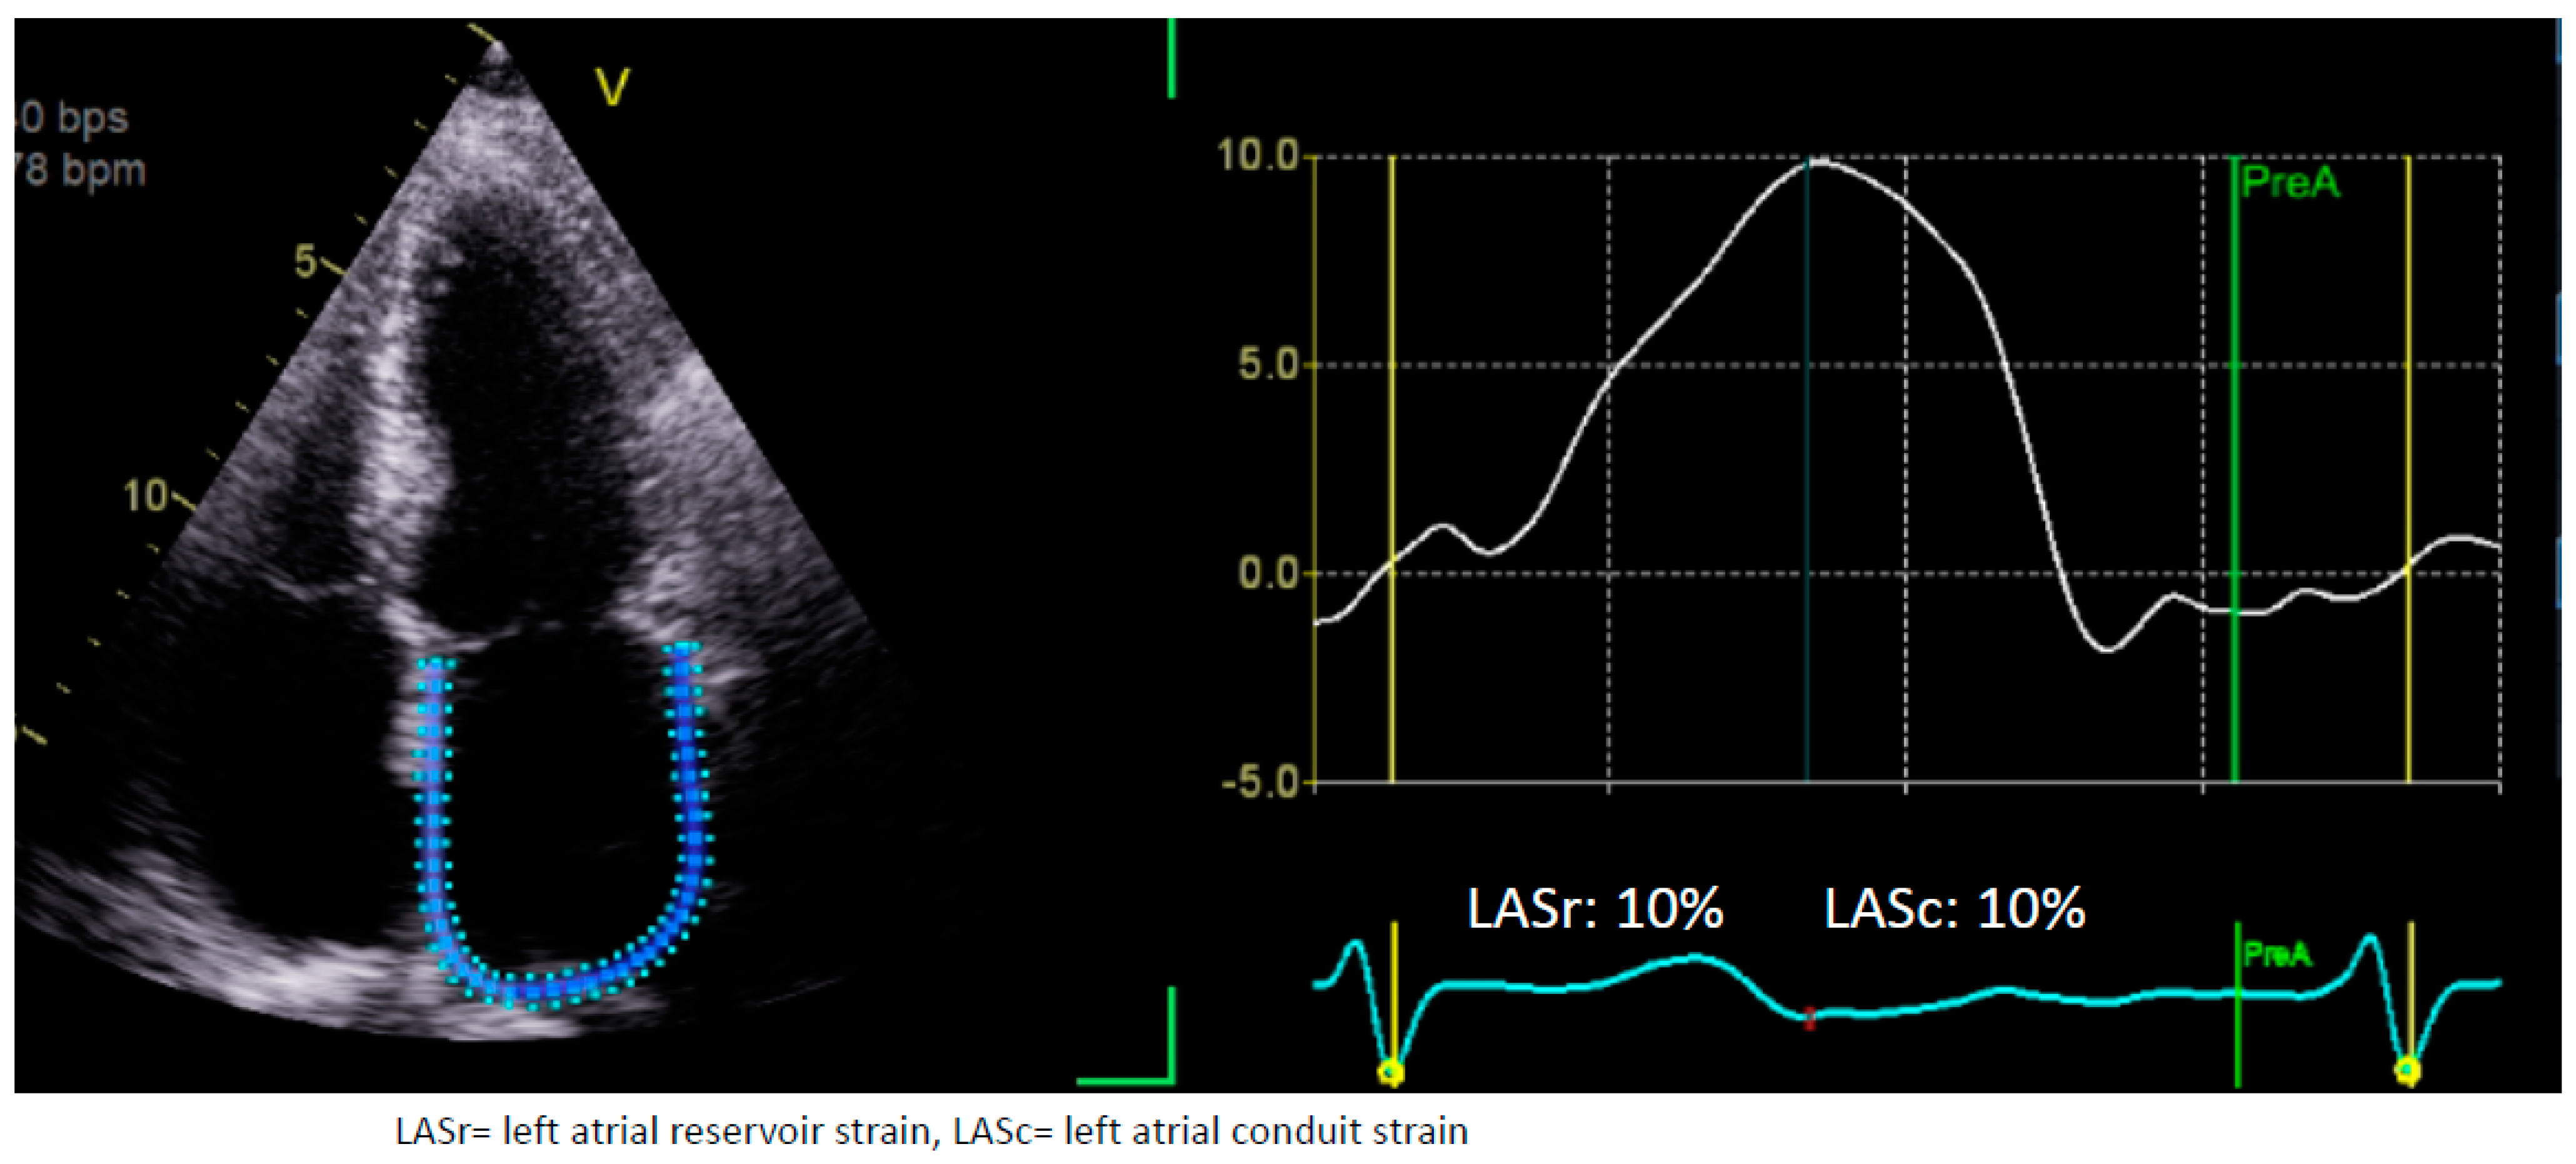

1.1. Assessment of LA Strain